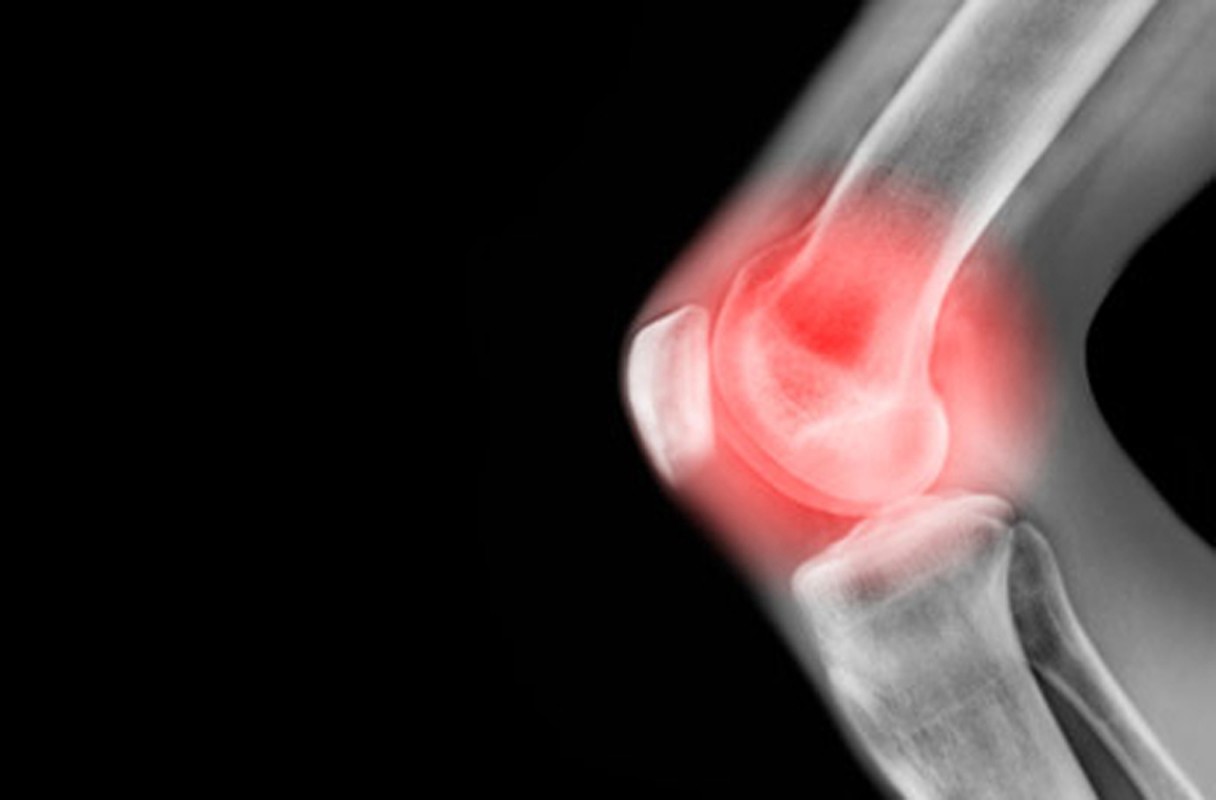

Ngoài công dụng ngăn ngừa ung thư, khoai môn có khả năng điều hòa huyết áp - lượng đường trong máu; chữa tiểu đường; thận và các bệnh về viêm khớp, u hạch.